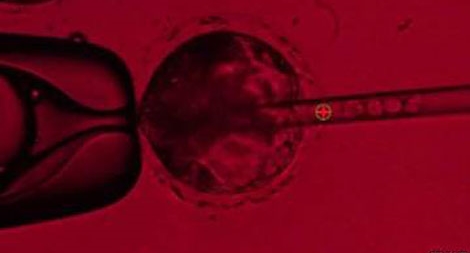

Các nhà khoa học thuộc Đại học California (Mỹ) đang cố gắng thử nghiệm nuôi cấy bộ phận cơ thể người bên trong cơ thể lợn bằng phương pháp tiêm tế bào gốc người vào phôi thai lợn để tạo ra phôi thai người-lợn giống như sinh vật thần thoại gọi là chimera.